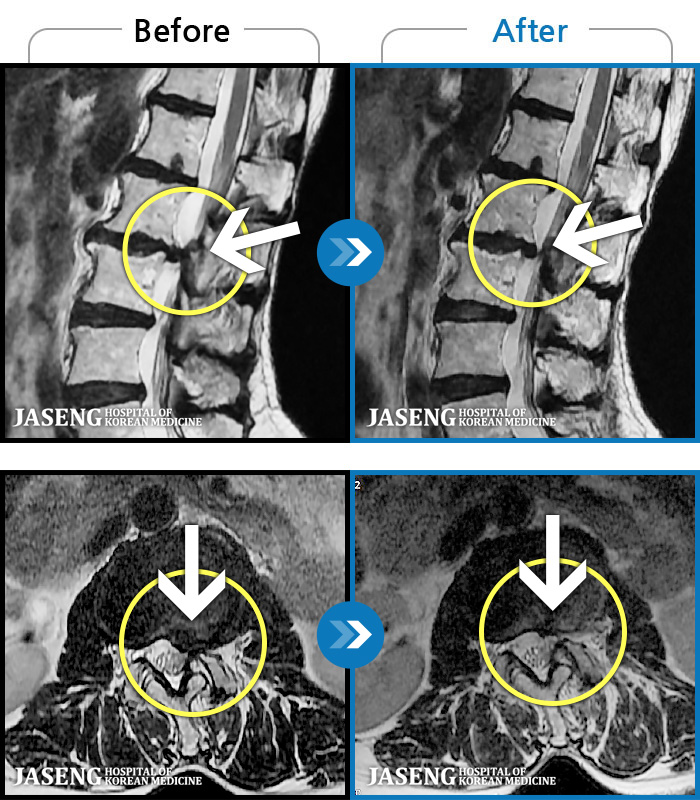

내일이면 퇴원이다. 3월부터 주위에서 허리통증 치료 잘 한다는 통증의학과ㆍ신경외과ㆍ정형외과 병원 3곳을 돌아다니며 허리 신경주사 12번 ,도수치료 10번, 물리치료 등등 정알 여러가지를 받았다. 그러나 치료와 처방 받은 진통제만으로는 일상생활을 하기가 많이 힘들었다. X레이 사진으로 확인한 척추 전방전위증은 결국은 수술을 받아야 한다고 하였다.

전방전위 대해 알아보다가 자생병원 홈페이지에서 김상돈 병원장님이 임상치료 하셨다는 것을 보고 잠시의 망설임도 없이 전화 예약하고 입원 하게 되었다.

MRI 검사로 정확한 진단을 시작으로 병원장님의 치료를 2주간 받았다. 친절한 설명과 따뜻한 배려로 정말 마음 편하게 치료 받을수 있었다.